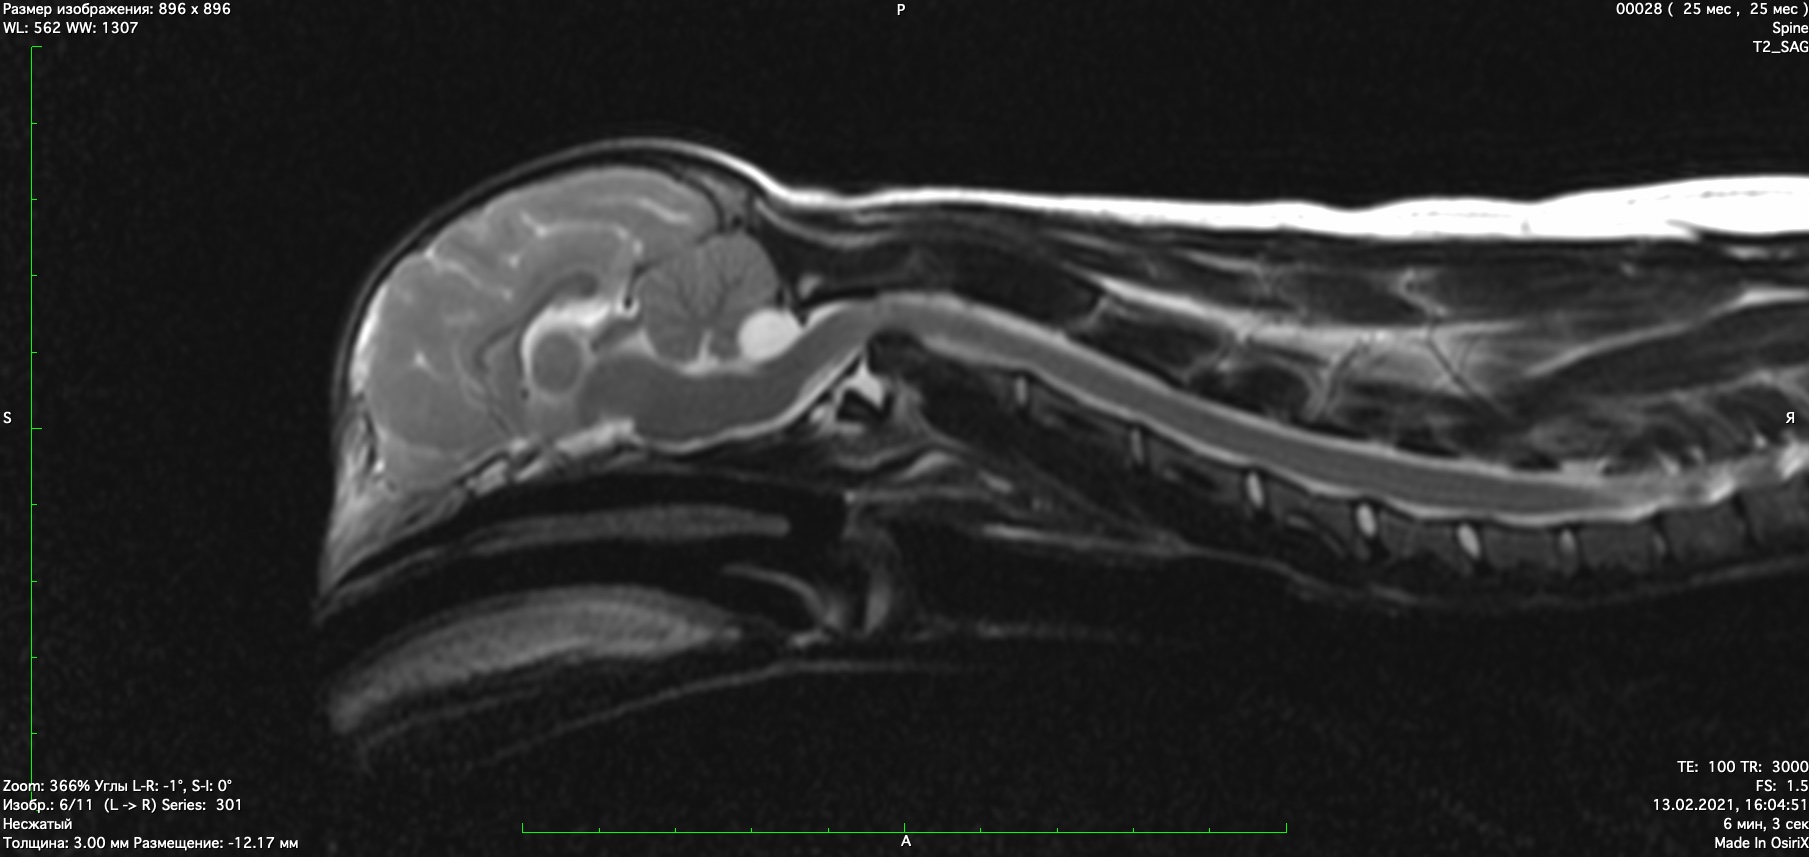

При проведении мрт диагностики установлено смещение второго шейного позвонка с компрессией спинного мозга, аплазия зуба второго шейного позвонка